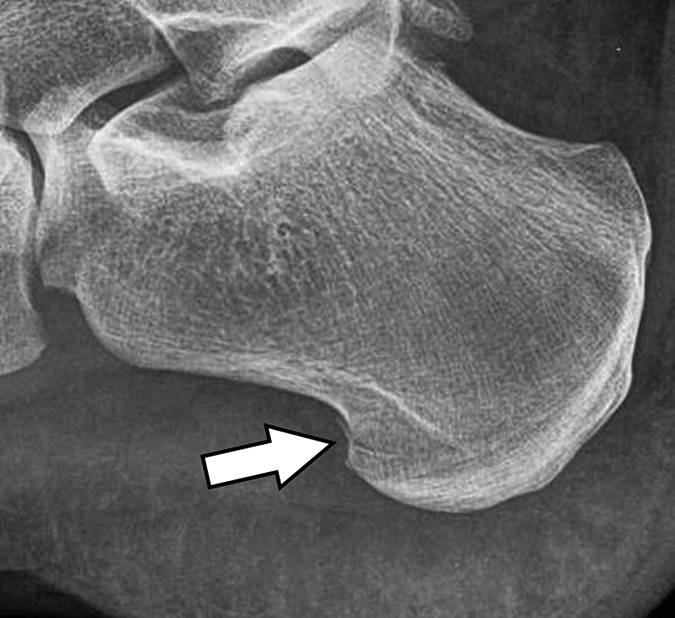

图 5B - 27岁的男性棒球运动员在运动加速后急性足跟疼痛。 侧位X线照片显示内侧足底过程中的线性断裂(箭头)。